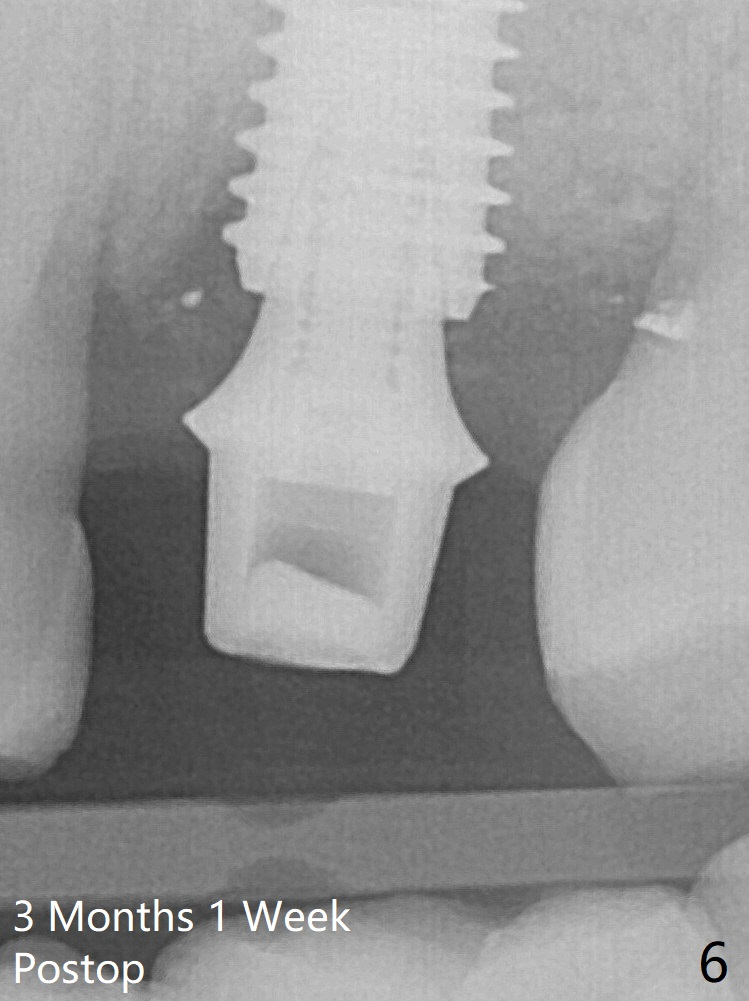

Further pushing of the bone graft from the buccal and palatal socket gaps results in more ideal packing (Fig.5 >).  If the bone graft were placed first, packing would have been easier.  An immediate provisional is fabricated to prevent further mesial shifting of the 3rd molar (Fig.1 arrow).  The implant remains stable, while the provisional and abutment are loose 3 months 1 week postop (Fig.6).  Impression is taken after abutment cleaning and retightening.